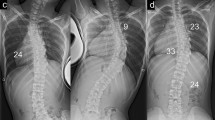

A 17-year-old girl underwent SDRRT. The MT curve was 51° (T5–L1), TK was 9°, and the apex of the MT curve was T9 preoperatively. At the final follow-up, the MT curve was 8° (T5–L1), TK was 18°, and the apex of TK was at T9 (Fig. 2).

Whole-standing spine radiographs of representative cases of thoracic adolescent idiopathic scoliosis prior to surgery and at final follow-up. A 17-year-old girl who underwent surgery using the simultaneous double-rod rotation technique (SDRRT) (A, B); a 13-year-old girl who underwent anatomical spinal reconstruction (ASR) with notched rods (C, D); and a 13-year-old girl who underwent ASR with notch-free rods (E, F).

A 13-year-old girl underwent ASR with notched rods. The MT curve was 50° (T6–L1), TK was 17°, and the apex of the MT curve was T9 in the preoperative period. The MT curve was 8° (T6–L1), the TK was 24°, and the apex of the TK was at T6 at the final follow-up (Fig. 2).

A 13-year-old girl underwent ASR with notch-free rods; the MT curve was 52° (T5–12), the TK was 12°, and the apex of the MT scoliosis was T9 in the preoperative period. The MT curve was 13° (T5–12), the TK was 30°, and the apex of the TK was at T6 at the final follow-up (Fig. 2).